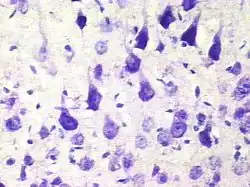

Пирамидальный нейрон

Пирамидальные нейроны, или пирамидные нейроны — основные возбудительные нейроны мозга млекопитающих. Также обнаруживаются у рыб, птиц, рептилий. Напоминают по форме пирамиду, из которой вверх ведёт большой апикальный дендрит; имеют один аксон, идущий вниз, и множество базальных дендритов. Впервые были исследованы Рамон-и-Кахалем. Отмечены в таких структурах, как кора мозга, гиппокамп, миндалевидное тело (амигдала), но отсутствуют в обонятельной луковице, стриатуме, среднем мозге, ромбовидном мозге, спинном мозге. В кортикальных структурах млекопитающих представляют наиболее многочисленную популяцию возбудительных нейронов.